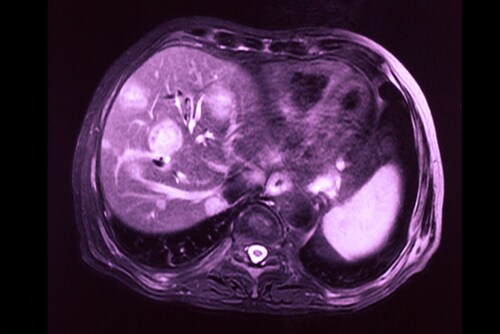

Hepatocellular carcinoma is one of the most common forms of liver cancer and has a poor prognosis. Local ablation therapy with transarterial chemoembolization (TACE), a method whereby the blood supply to the tumor is restricted, is unfortunately associated with cholangiocellular differentiation in hepatocellular carcinoma. A potential explanation for this is that TACE provides selection pressure in favor of this particular cell population, which may be resistant to TACE.1 In the absence of biomarkers to differentiate between hepatocellular carcinoma and cholangiocarcinoma tumors or any real understanding of the pathogenesis of these types of tumors, treatment is a challenge and options remain few.

Building on their earlier research,1 Zen et al. recently profiled the protein expression of chemo-resistant, mixed-phenotype liver tumors to identify biomarkers for clinical use and better understand the pathogenesis of differentiation.2 The investigators used 55 human tissue samples from nine different types of liver tissue. The tissue types they used for differentiation were as follows: mixed hepatocellular carcinoma/cholangiocarcinoma after TACE (the researchers examined the areas of hepatocellular carcinoma and areas of cholangiocarcinoma separately), non-treated hepatocellular carcinoma, normal liver parenchyma, normal bile duct, non-treated peripheral cholangiocarcinoma, non-treated hilar/perihilar cholangiocarcinoma, PSC-associated hilar cholangiocarcinoma, and metastatic colorectal cancer.